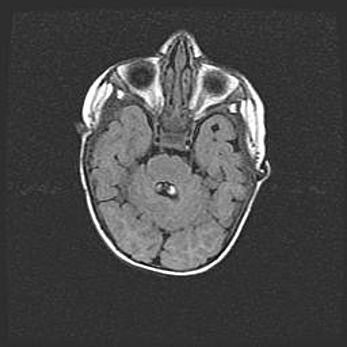

Наружная гидроцефалия с возможной атрофией височных областей.

Возраст: 28 дней

Вес: 3670 г

Пол: мужской

Окружность головы: 38 см

Срок гестации: 40 недель

Гидроцефалия головного мозга у новорожденных – это заболевание, которое характеризуется скоплением избыточного количества спинномозговой жидкости в желудочковой системе головного мозга в результате затруднения её перемещения от места выработки к месту поглощения в кровеносную систему или вследствие нарушения абсорбции. При открытой наружной форме гидроцефалии у новорожденных расширяются и переполняются субарахноидные пространства.

При нормотензивных  формах,  которые,  как  правило,  являются  следствием  перенесенных ишемических  повреждений  паренхимы  мозга,  возможно  сочетание микроцефалии  с нормотензивной гидроцефалией. В основе данных изменений лежит атрофия больших полушарий с преимущественной  локализацией  в  лобно-височных  областях.